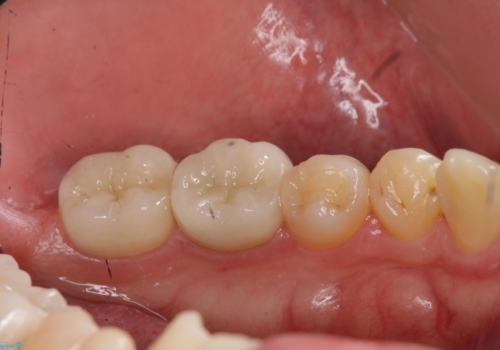

放置した虫歯の治療 親知らずの手前が虫歯

- 詰め物が取れて放置していたとのこと。

虫歯が大きかったため、被せ物(クラウン)としました。

親知らずを抜いてから治療しています。

幸い神経を取らずにすみました。